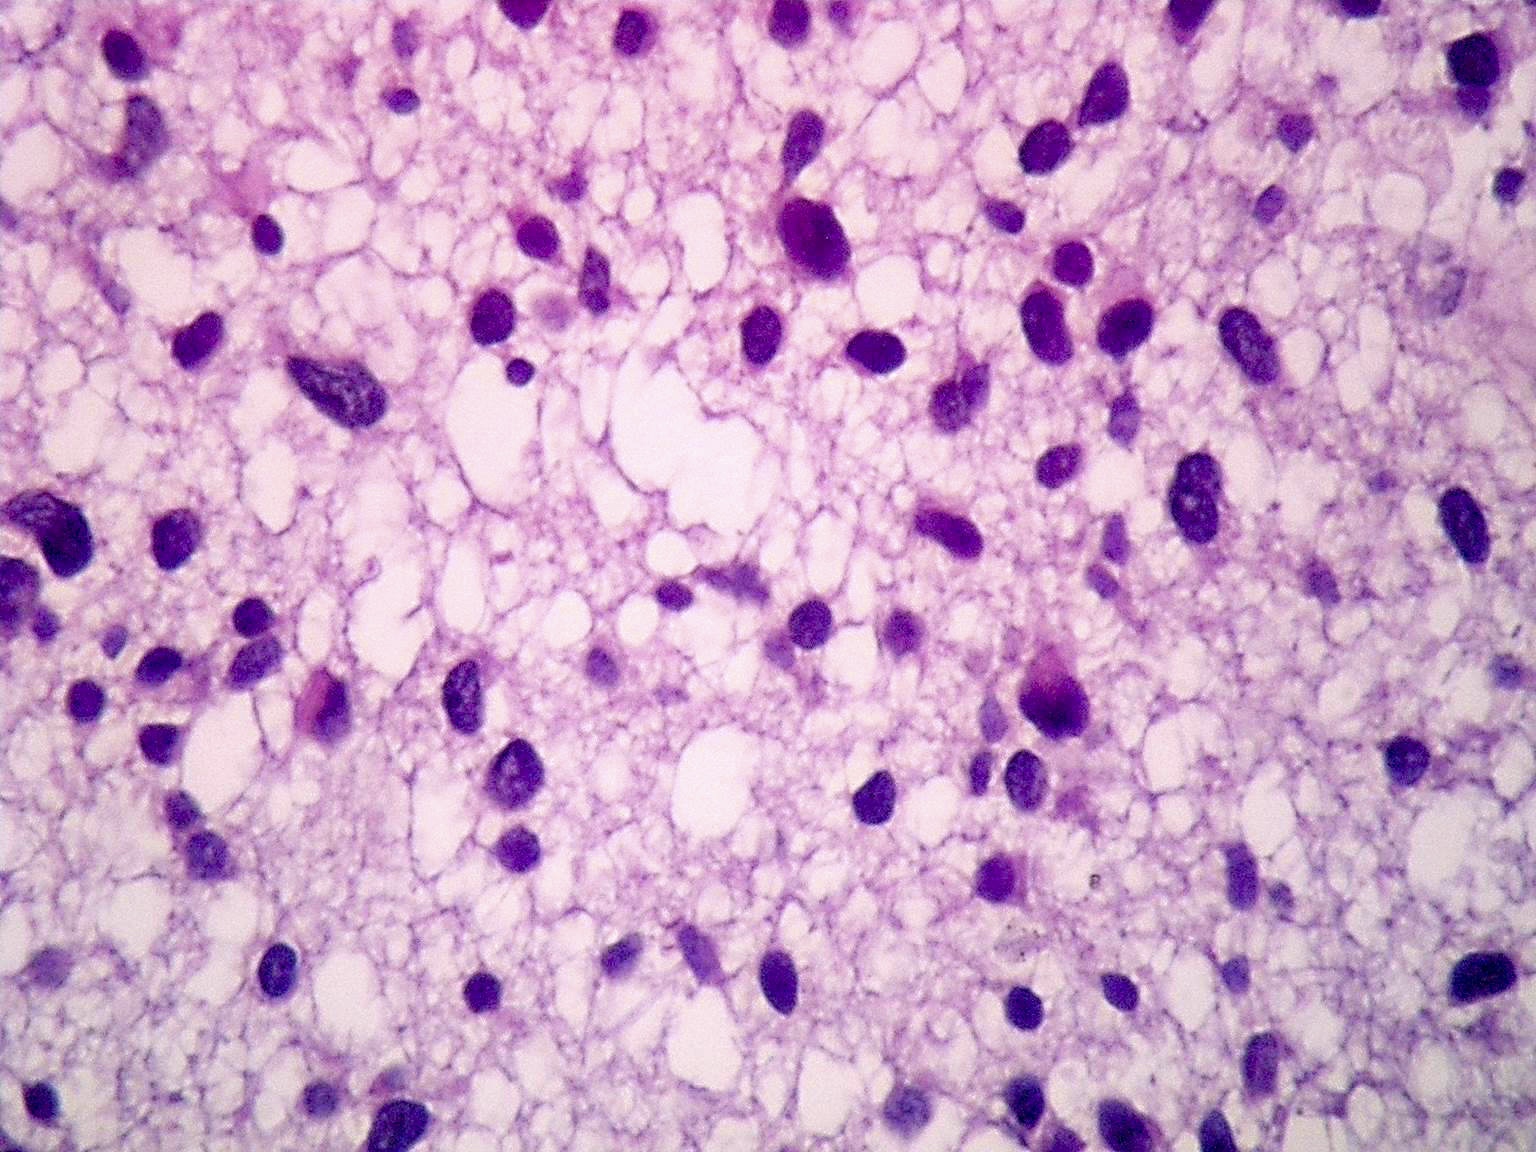

Frozen section description

- Smear done at the time of frozen section will show astrocytic appearing tumor cells with oblong irregular nuclei with varying degrees of atypia and glial processes

- High grade nuclear features and mitotic activity may be observed on frozen section but necrosis or microvascular proliferation (features of glioblastoma) should not be present

- Cellular morphology can be highly variable

- Often predominantly tumor cells with oval hyperchromatic nuclei in a fibrillary background

- Variably present, larger cells and pleomorphism

- Variable quantity of cells with eccentric nuclei and glassy eosinophilic cytoplasm (gemistocytes)

- Some show predominantly small cells with little pleomorphism and scant cytoplasm

- Sections are hypercellular showing infiltrating neoplastic cells with edema

- Variably present mitotic figures, necrosis and microvascular proliferation

- Vascular thromboses and myxoid background may be present

- Smear most commonly shows predominantly smaller cells with fine fibrillar processes, elongated nuclei, nuclear atypia and may show mitotic figures

Intraoperative frozen / smear cytology images

Microscopic (histologic) description

- Diffusely infiltrating tumor cells with oval to elongated astrocytic nuclei and varying appearance of tumor cytoplasm and fibrillar glial processes (Acta Neuropathol 2015;129:789)

- At the periphery, tumor cells may infiltrate in a diffuse single cell pattern, often with entrapped neurons and axons

- Cellular morphology is variable, even within a single tumor

- Commonly there is a mix of cells with elongated nuclei and fine fibrillar processes, cells with eccentric nuclei and glassy eosinophilic cytoplasm (gemistocytes), larger pleomorphic cells and small cells with scant cytoplasm

- May show oligodendroglioma-like areas

- Myxoid background and microcyst formation may be present

- Variable mitotic activity, cellularity and nuclear atypia depending on CNS WHO grade

- In small biopsy specimens, the presence of 1 mitosis may be sufficient for a CNS WHO grade 3 diagnosis, while the presence of a few mitotic figures in a large resection would not be sufficient for grade 3 designation (Acta Neuropathol 2020;139:603)

- Presence of necrosis or microvascular proliferation would be consistent with a CNS WHO grade 4 designation

Microscopic (histologic) images

Contributed by Eman Abdelzaher, M.D., Ph.D., John DeWitt, M.D., Ph.D. and Meaghan Morris, M.D., Ph.D.

Which of the following is true about the entity in the figure above presenting in a 50 year old man?

B. If R132H IDH1 immunohistochemistry is positive, ATRX staining of tumor cells is expected to be lost. The image is consistent with an infiltrating astrocytoma with significant pleomorphism and mitotic activity. If R132H IDH1 immunohistochemistry is positive, as stated in answer B, the findings are then consistent with astrocytoma, IDH mutant, CNS WHO grade 3. Astrocytoma, IDH mutant tumors often show concurrent ATRX mutation, indicated by loss of staining in tumor cells with ATRX immunohistochemistry.